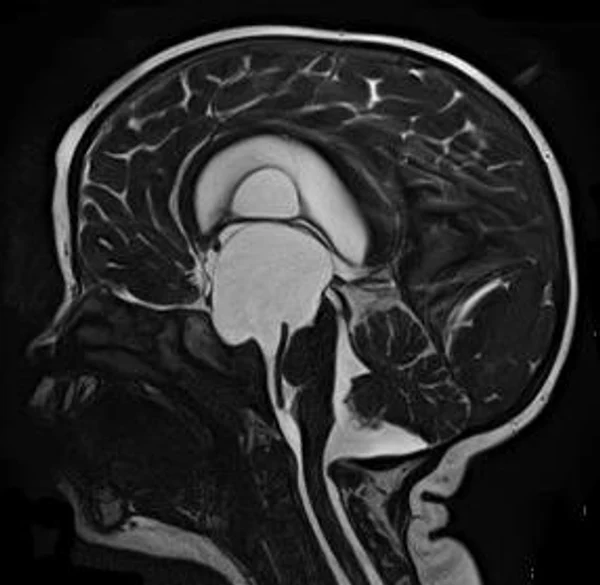

кисты, аномалии Денди-Уокера и др.Операции при внутричерепных кистах. В основном встречаются арахноидальные кисты различных локализаций и кисты сосудистых сплетений боковых желудочков. Пациентам с врождёнными кистами операции проводятся в следующих ситуациях: увеличении объема кисты в динамике, наличии клинических проявлений, компрессии и дислокации мозговых структур, наличии окклюзии ликворных путей. Нами используются 2 способа хирургического лечения кист: эндоскопическая перфорация стенок кист и открытая резекция кист. Открытая резекция кист проводится при ретроцеребеллярных арахноидальных кистах (рис. 2), при арахноидальных кистах межполушарной щели при отсутствии непосредственного контакта их стенок со стенками расширенных желудочков головного мозга и повторного увеличения кист средней черепной ямки после эндоскопической кисто-цистерностомии. Техника операции заключается в проведение краниотомии и максимальном иссечении стенок кист с созданием широкого сообщения кист с субарахноидальным пространством. Эндоскопические операции проводятся при арахноидальных кистах межножковой и пинеальной цистерн, арахноидальных кистах межполушарной щели при тесном контакте их стенок со стенками расширенной желудочковой системы (рис. 3), первично при арахноидальных кистах средней черепной ямки, а также при кистах сосудистых сплетений боковых желудочков. При арахноидальных кистах межножковой цистерны эндоскопически проводится перфорация стенок кисты, сообщая ее с просветом III желудочка и межножковой цистерной – эндоскопическая вентрикуло-кисто-цистерностомия (рис. 4). При арахноидальных кистах пинеальной цистерны проводится перфорация кисты в передне-верхних её отделах с созданием сообщения полости кисты с просветом III желудочка – эндоскопическая кисто-вентрикулостомия. С целью предотвращения облитерации сформированного отверстия иногда в полость кисты под контролем эндоскопа вводится стент перфорированный на протяжении (рис. 5, 6). Эндоскопическая кисто-цистерностомия выполняется при арахноидальных кистах средней черепной ямки. При этом создается широкое сообщение кисты с базальными цистернами. При кистах сосудистых сплетений боковых желудочков проводится их вскрытие в просвет боковых желудочков – эндоскопическая кисто-вентрикулостомия. При множественных кистах проводится их хирургическое сообщение между собой – интеркистосмия